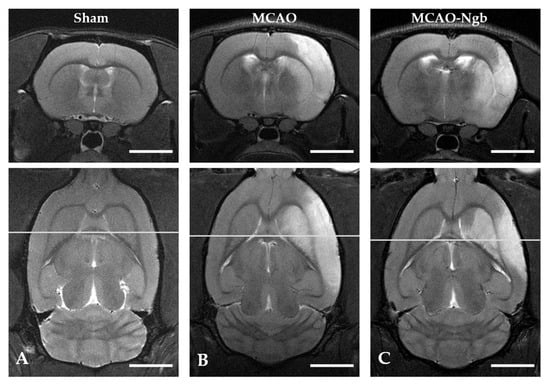

2.3. Ngb-NPs Treatment does not Affect the Infarct Size or the Oxidative/Nitrosative Stresses, but Improves the Histological Outcomes

4.6. MRI Neuroimage Study